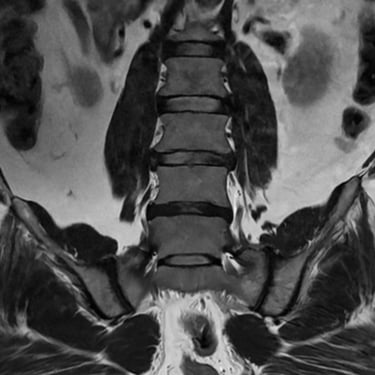

Inestabilidad de la Columna Lumbar: Tratamiento con Fijación Transpedicular y TLIF

La inestabilidad de la columna lumbar ocurre cuando los segmentos vertebrales pierden su alineación y soporte normal, generando dolor lumbar crónico, limitación funcional y, en algunos casos, compresión de las raíces nerviosas. Cuando el tratamiento conservador no resulta efectivo, la fijación transpedicular (FTP) asociada a la fusión intersomática transforaminal (TLIF) representa una alternativa quirúrgica eficaz. Este procedimiento permite estabilizar el segmento afectado, descomprimir las estructuras nerviosas y restaurar la biomecánica de la columna. La combinación de fijación y fusión reduce el dolor, mejora la estabilidad vertebral y favorece una recuperación funcional segura y progresiva.